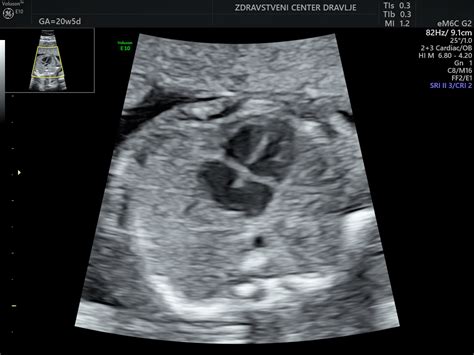

Prirojene srčne napake so med vsemi prirojenimi napakami organov in organskih sistemov najpogostejše. Nekatere napake so razmeroma blage in bolnikom nikoli ne povzročajo težav, pri polovici bolnikov pa so napake takšne, da jih je potrebno z operacijo ali intervencijskim posegom zdraviti že v prvem letu življenja, ali pa bolniki umrejo. Vsako leto se tako v Sloveniji s srčno napako rodi približno 140 otrok in polovica od teh bo potrebovala operacijsko ali intervencijsko kardiološko zdravljenje še preden bodo shodili. Večino pomembnih srčnih napak je z ultrazvočnim pregledom plodovega srca mogoče ugotoviti in opredeliti že pred 20. Ultrazvočni pregled plodovega srca je preiskava, ki se opravi v primerih, ko ima nosečnica povečano tveganje za rojstvo otroka s srčno napako in v primerih, ko na srčno napako posumi ginekolog ob presejalnem ultrazvočnem pregledu ploda na prirojene nepravilnosti. Pregled opravi posebej specializiran kardiolog, ki ga imenujemo tudi »fetalni kardiolog«, in je potreben tudi ob ugotovljeni genetski napaki ali ugotovljeni razvojni nepravilnosti drugih organov in organskih sistemov. Tveganje za rojstvo otroka s srčno napako je večje, če ima napako eden od staršev ali sorojencev, kakor tudi ob sladkorni bolezni in še nekaterih drugih presnovnih boleznih pri materi. Tveganje za rojstvo otroka s srčno napako se poveča tudi ob jemanju nekaterih zdravil, ter ob izpostavljenosti škodljivim vplivom okolja in nekaterim infekcijam. V večini navedenih primerov je tveganje sicer povečano, vendar ne presega več kot 3 odstotke. Bolniki, ki jih razpoznamo na podlagi povečanega tveganja za rojstvo otroka s srčno napako, so redki in ne predstavljajo več kot le nekaj odstotkov vseh bolnikov s srčnimi napakami. Večina bolnikov se tako rodi staršem brez izstopajočih dejavnikov tveganja. V zadnjih nekaj letih se je kot dodatna presejalna metoda za razpoznavo plodov s povečanim tveganjem za srčno napako, uveljavilo merjenje nuhalne svetline. Merjenje nuhalne svetline, ki predstavlja razdaljo med kožo in mehkimi tkivi, ki pokrivajo hrbtenico, izvajajo ginekologi med 11. in 14. tednom nosečnosti. Metodo, pri kateri izmerjeno vrednost nuhalne svetline kombiniramo s starostjo nosečnice, so razvili predvsem za oceno tveganja za prisotnost trisomije 21 (Downovega sindroma), kmalu pa so ugotovili, da je nuhalna svetlina razen pri kromosomskih nepravilnostih povečana tudi pri plodovih s srčno napako. Čeprav je mogoče plodovo srce ultrazvočno pregledati in oceniti že okoli 16. tedna nosečnosti, največ pregledov opravimo pri nosečnicah med 20. in 22. tednom nosečnosti. Srce je v tem času veliko približno kot lešnik. Pregled začnemo z oceno velikosti srca in njegove lege v prsnem košu. Prikažemo priliv obeh votlih ven v desni preddvor ter priliv vsaj ene pljučne vene v levi preddvor. Razpoznamo oba preddvora in prekata ter ocenimo delovanje trikuspidne in mitralne zaklopke. Prikažemo in vrednotimo tudi ovalno okence in Botallov vod. Obe strukturi sta pri plodu široko odprti, po rojstvu pa se zapreta. Poleg same morfologije ocenimo ob ultrazvočnem pregledu plodovega srca še funkcijo srčne mišice in opredelimo srčni ritem. Predrojstno svetovanje je bistven del kardiološkega pregleda otroka v maternici. V pogovoru nikoli ne hitimo, staršem moramo omogočiti dovolj časa, da se soočijo z okoliščinami, v katerih so se znašli. Na podlagi ugotovljene srčne napake se s perinatologi dogovorimo za usmerjen ultrazvočni pregled za izključitev drugih prirojenih nepravilnosti ter izvedbo smiselnih genetskih preiskav. Pomembno je, da so informacije, na podlagi katerih se starši odločijo glede nadaljevanja prizadete nosečnosti, realne in čim bolj popolne. Odločitev glede nadaljevanja oziroma prekinitve nosečnosti, ki jo starši sprejmejo v okviru obstoječe pravne ureditve, kot tako sprejmemo in podpremo. Skladno z naravo srčne napake perinatologu svetujemo glede termina in načina poroda, neonatologu pa glede morebitnih nujnih ukrepov, ki bodo pri novorojencu potrebni v prvih urah življenja. Predrojstna razpoznava je zato zlasti pomembna pri tistih napakah, pri katerih se ob zapiranju Botallovega voda bistveno zmanjša pretok krvi skozi telo ali pljuča, kar privede do zakisanja tkiv in krvi, v skrajnih primerih pa tudi do smrti bolnika. S pravočasnim dajanjem zdravil, ki preprečijo zaprtje Botallovega voda, pridobimo čas, ki je potreben za izvedbo intervencijskega ali kirurškega zdravljenja, s katerim bolnikovo stanje stabiliziramo oziroma napako v celoti odpravimo. V Sloveniji se diagnostika srčnih napak pred rojstvom ter diagnostika in zdravljenje motenj srčnega ritma pri plodu izvajata v okviru Centra za fetalno kardiologijo, ki deluje v okviru Službe za kardiologijo Pediatrične klinike v Ljubljani. V okviru Centra vsako leto obravnavamo približno 300 nosečnic, pri katerih je povečano tveganje za rojstvo otroka s srčno napako, ali pa na srčno napako ob presejalnem ultrazvočnem pregledu posumijo ginekologi. Pomembno srčno napako ugotovimo pri 15 do 20 plodovih, število odkritih napak pa se iz leta v leto povečuje. Letno v Centru obravnavamo in zdravimo tudi 5 plodov z motnjami srčnega ritma, predvsem fetalno tahikardijo in kompletnim srčnim blokom. V razvitih zdravstvenih sistemih se težišče razpoznave prirojenih srčnih napak iz obdobja po rojstvu vedno bolj pomika v čas druge tretjine nosečnosti. Prednosti zgodnje razpoznave so številne. V zadnjih nekaj letih smo se z vztrajnim delom ter dobrim sodelovanjem med pediatričnimi kardiologi in perinatologi tem trendom uspeli priključiti tudi v Sloveniji.

- Ultrazvok srca (Ehokardiografija): Izvede se po potrebi, zlasti pri sumu na strukturno bolezen srca. Omogoča oceno morfologije srca, funkcije srčne mišice in srčnega ritma. V primeru sumljivih izvidov ali tveganja za srčno napako pri plodu je ključnega pomena fetalna ehokardiografija.

V primerih, ko obstaja povečano tveganje za rojstvo otroka s srčno napako (npr. družinska anamneza, genetske nepravilnosti, določene okužbe ali izpostavljenost škodljivim snovem med nosečnostjo), se opravi ultrazvočni pregled plodovega srca. Ta pregled, ki ga opravi fetalni kardiolog, omogoča zgodnjo diagnozo in načrtovanje ustreznega vodenja nosečnosti in poroda. V Sloveniji se diagnostika srčnih napak pred rojstvom ter diagnostika in zdravljenje motenj srčnega ritma pri plodu izvajata v okviru Centra za fetalno kardiologijo Pediatrične klinike v Ljubljani.